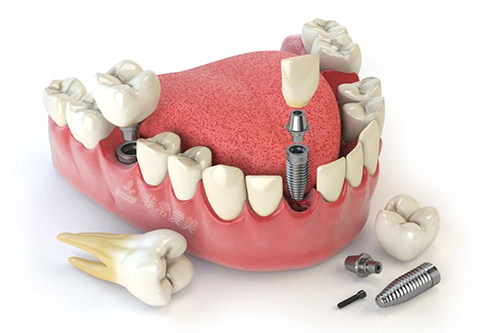

无论是牙齿矫正、种植牙还是口腔修复等项目,都能取得稳定的治疗结果。